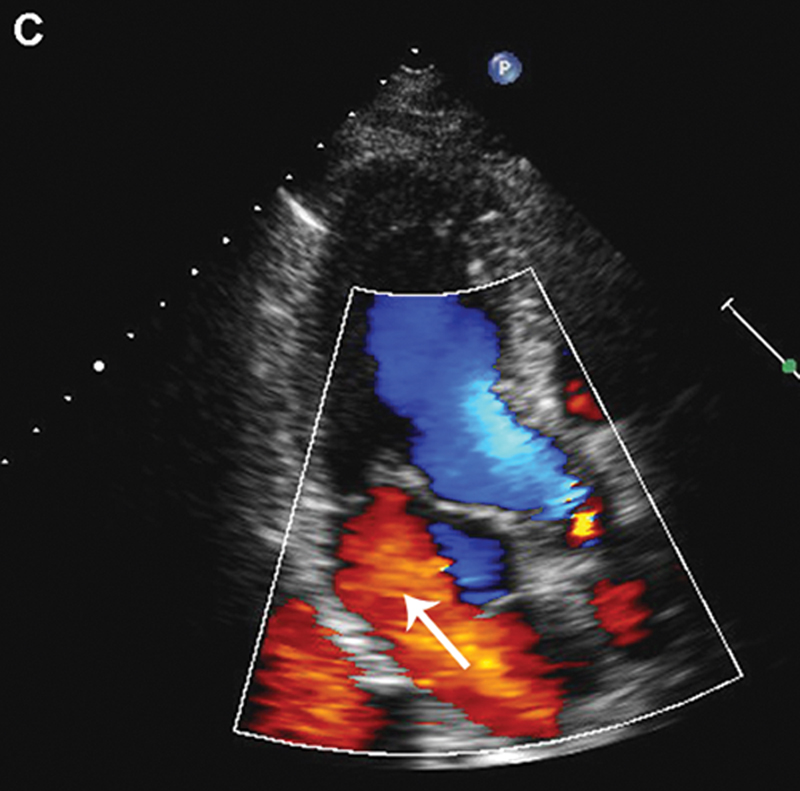

فحوصات تشخيصية لبعض امراض القلب والشرايين التاجية